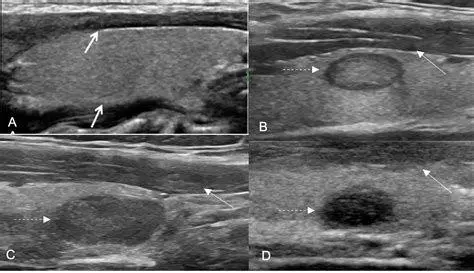

- Pencitraan (Imaging): Seperti USG leher, CT Scan, atau MRI untuk melihat struktur internal benjolan secara detail.

- Biopsi Aspirasi Jarum Halus (BAJH/FNAB): Pengambilan sampel sel menggunakan jarum kecil untuk diperiksa di bawah mikroskop oleh dokter patologi anatomi. Ini adalah standar emas untuk membedakan sel jinak dan ganas.